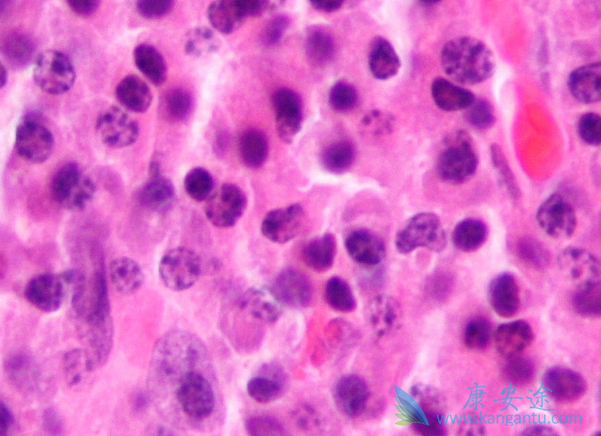

骨髓瘤,是一种恶性肿瘤,是长在骨髓中的一种恶性肿瘤。由于恶性浆细胞瘤有部分长在骨髓里,有一部分是在骨髓外,一半患者在抽骨髓时会发现,因此骨髓瘤也是一种恶性浆细胞瘤。那临床上骨髓瘤症状表现有那些呢?由于骨髓瘤占领了骨髓造血空间,所以60%的患者会出现贫血症状。还有一部分患者会出现不同程度的骨痛。